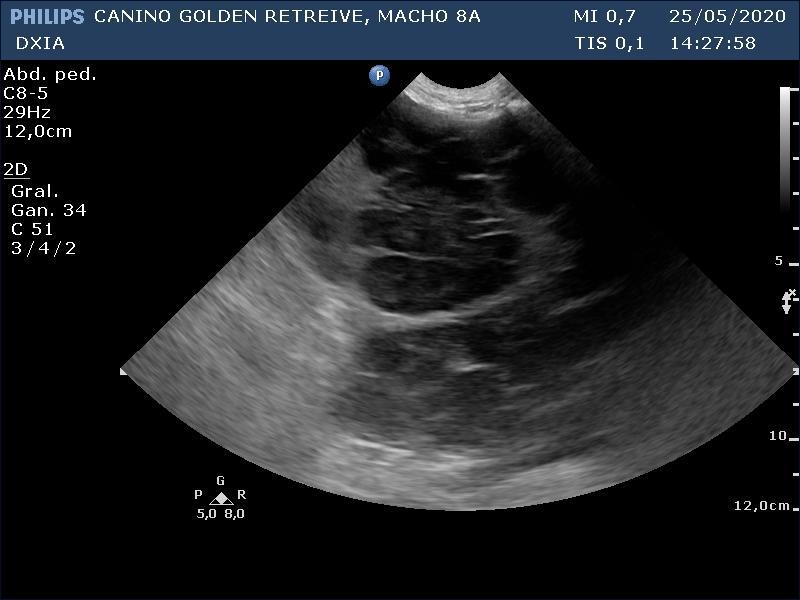

En el ecocardio, gráficamente no hay alteraciones. En la ecografía abdominal, hay gran distensión por presencia de líquido libre abdominal y alteración de todo el parenquima hepático (patrón modular marcado) con hepatomegalia.

SCOTT_CANINO GOLDEN RETREIVE-desenlace01

SCOTT_CANINO GOLDEN RETREIVE-desenlace02

SCOTT_CANINO GOLDEN RETREIVE-desenlace03